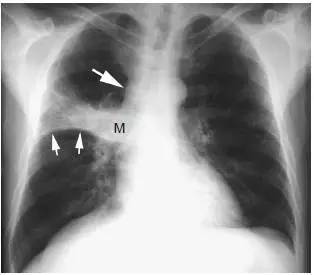

图2 鳞状细胞癌伴支气管阻塞和肺不张

胸片显示右肺门大肿块(M) 伴水平裂向上弯曲移位( 小箭头)。呈反“S”征,可见纵隔淋巴结增大( 大箭头)